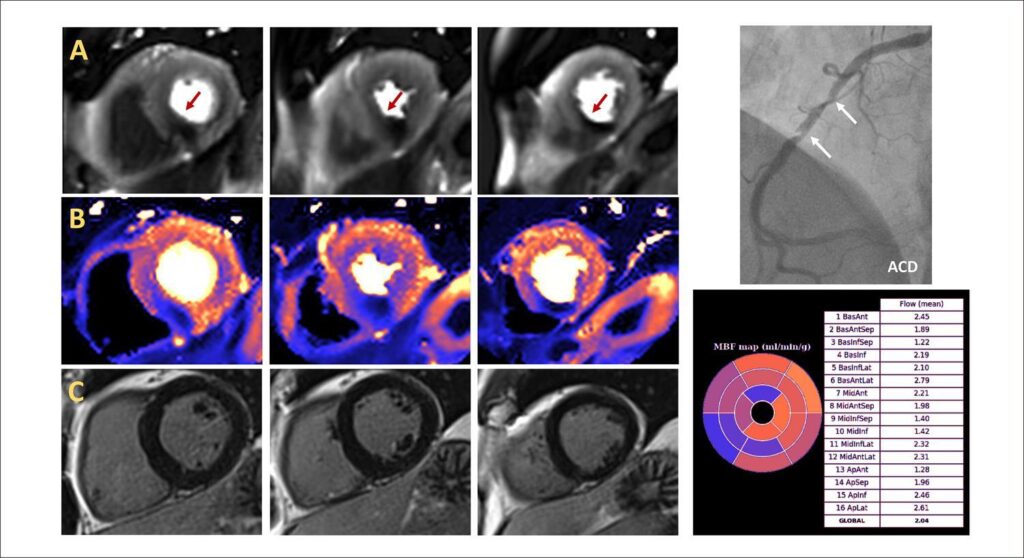

Imagem Não Invasiva Contemporânea na Síndrome Coronariana Crônica: O que a Ressonância Magnética Cardiovascular de Estresse Tem a Oferecer

A imagem cardíaca não invasiva possui um papel diagnóstico e prognóstico estabelecido em pacientes com doença cardíaca isquêmica suspeita ou conhecida, e a tecnologia de imagem evoluiu tem evoluído significativamente ao longo dos anos. A ressonância magnética cardiovascular (RMC) surgiu como uma modalidade robusta de imagem diagnóstica e prognóstica e atualmente representa uma alternativa válida a outras técnicas existentes e bem validadas, mas também surgiu como uma possível estratégia de primeira linha.

As principais diretrizes de prática clínica têm cada vez mais incorporado a RMC de estresse como um teste clínico indicado para pacientes com dor torácica. A RMC de estresse recebeu recomendação de classe I pela primeira vez nas diretrizes da Sociedade Europeia de Cardiologia (ESC) de 2014 para revascularização, seguidas pelas diretrizes da ESC de 2017 no diagnóstico e tratamento do infarto do miocárdio com elevação do segmento ST, que tem recomendado a RMC como um teste alternativo para a função ventricular esquerda quando a ecocardiografia é subótima, mas também para a avaliação da viabilidade miocárdica e isquemia. As diretrizes da American Heart Association (AHA)/American College of Cardiology (ACC) recentemente publicadas em 2021 também indicam a RMC de estresse com recomendação de classe I para pacientes com dor torácica aguda e crônica e risco intermediário de doença arterial coronariana (DAC) ( ).